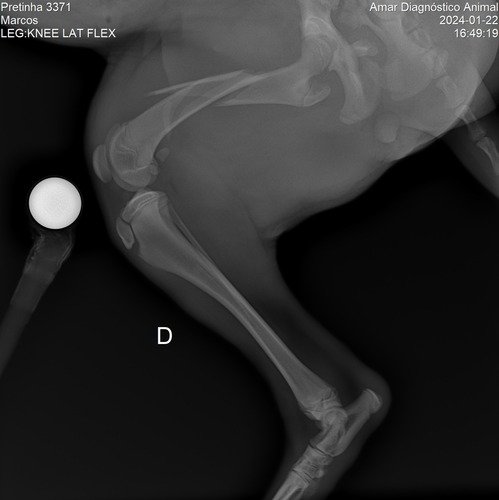

Meu nome é Flávia e moro aqui em Mogi Guaçu, interior de SP. No bairro onde eu moro infelizmente acontece muitos casos de abandono de animais, especialmente cachorros. Foi o caso dessa menininha linda da foto. Ela foi abandonada junto com sua mamãe e mais duas irmãzinhas. Infelizmente no último dia 21 de janeiro, a Belinha foi atropelada e o motorista fugiu sem prestar socorro. Depois de uma vaquinha comunitária e ajudas para as primeiras consultas e o Raio-X, foi constatada lesões na perninha direita, na bacia e baço, sendo então indicado um procedimento cirúrgico para que essa menininha amorosa possa continuar vivendo. Ainda não temos os custos finais para a cirurgia, mas certamente não sairá tão barato, pois além do procedimento também terá todo o processo do pós operatório. E é por isso que estamos abrindo essa Vakinha virtual para ajudar a custear a cirurgia e pós dela. Depois de recuperada, esperamos encontrar um lar lindo e feliz para ela, para sua irmãzinha e para sua mamãe. Nos ajude com qualquer valor. Caso consigamos algum excedente, vamos doar para ONGs que cuidam de animais aqui em nossa cidade. Que Deus os abençoe e guarde!!